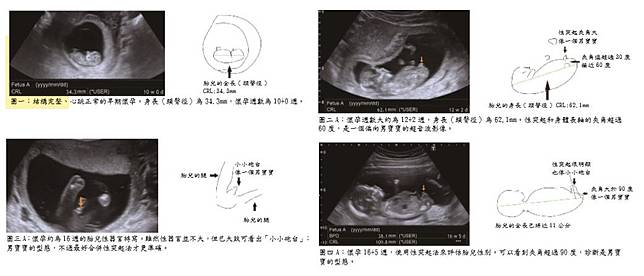

超音波檢查:懷孕12週後即可開始用超音波觀察胎兒性器官,但因為胎兒姿勢、肚皮厚度、機器解析度等因素,早期判斷可能有誤差。到了16週以上,尤其27~28週時,判斷準確率明顯提高,性別翻盤的機率幾乎不會發生。